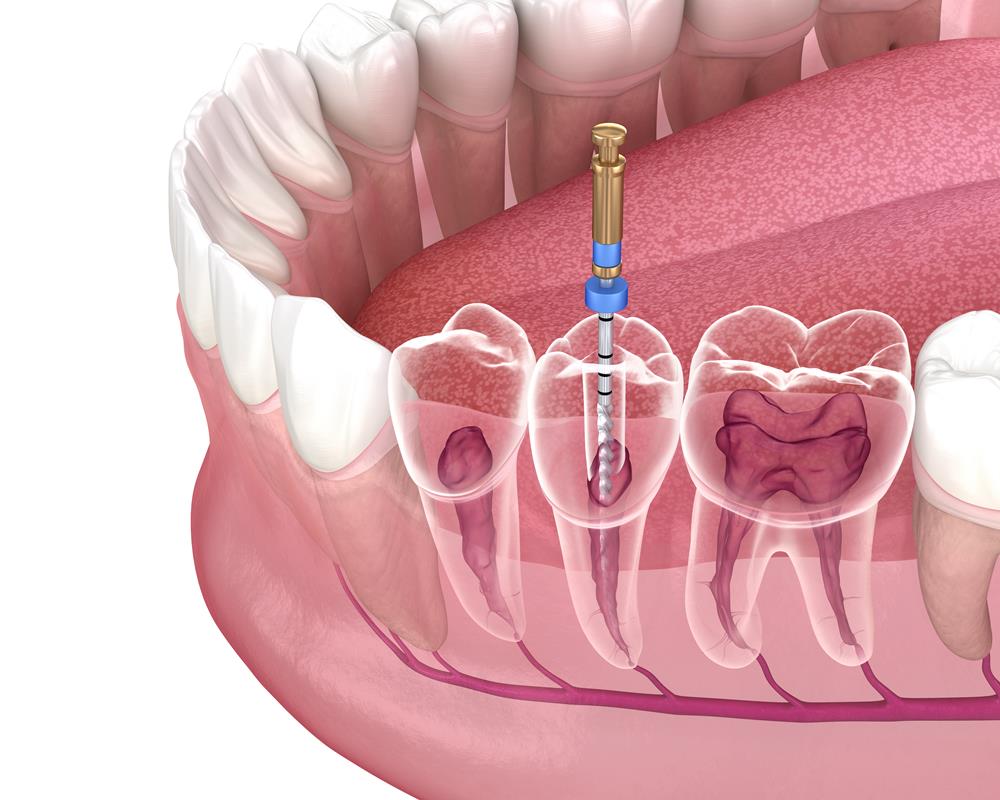

Much like a filling, there will need to be drilling involved in order to clean out the decayed area of the tooth. Luckily for you, you will receive a local anesthetic in order to numb the area that is being treated. The main difference is that the infected or damaged area is slightly deeper than your average filling situation. During the root canal procedure, the nerve and pulp are removed from the tooth. The pulp is a soft chamber where bacteria begin to quickly multiply when the damage reaches this level. If this is not cleaned out, then a deeper infection or abscess can form causing even more damage to your mouth.

After the pulp and nerve are removed from the damaged tooth, the dentist may either decide to immediately seal the tooth or wait, depending on the situation. Sometimes it is better for the tooth to heal with medication before sealing and other times it is better to quickly seal the tooth right after the procedure. To seal the tooth, a paste is placed into the root canal, which often consists of a rubber compound. Typically, when a root canal is needed, there will also be a large filling that needs to be placed as well. Many times a dentist will opt for using a dental crown in order to better cement the tooth in place if there isn’t much of the original tooth left. Thankfully, after this procedure is finished, you will be almost as good as new. The only thing that changes is you will not have nerves in that specific tooth to feel hot or cold. Everything else will be the same.